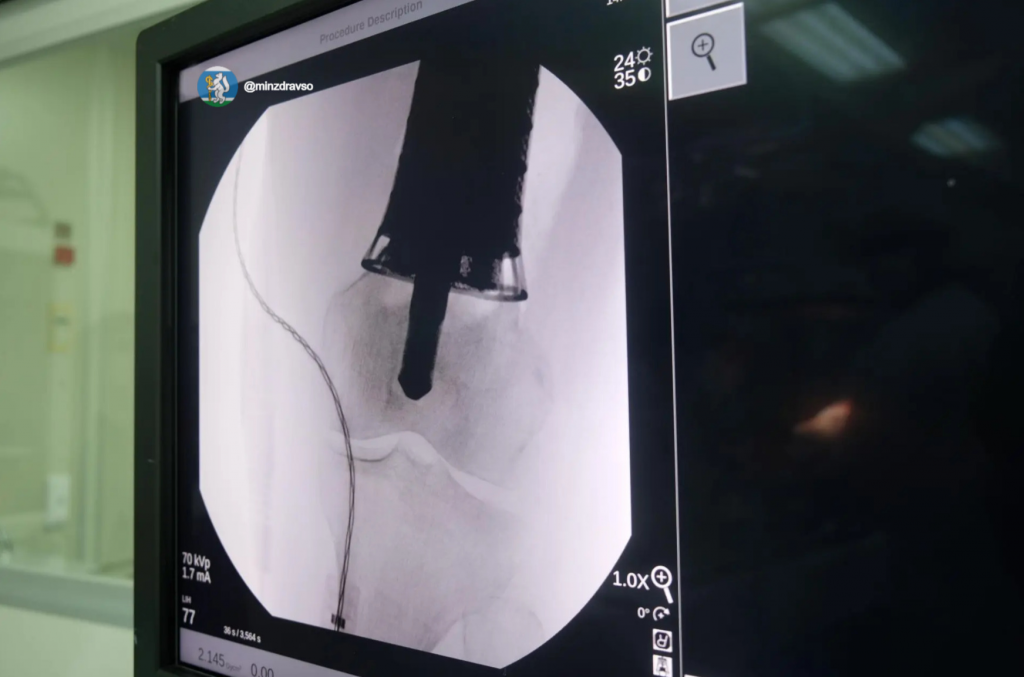

Одним из недавних подобных случаев стало выявление редкой опухоли у свердловчанки. Новообразование спровоцировало патологический перелом бедренной кости при обычной домашней нагрузке. После углублённой диагностики было принято решение провести органосохраняющую операцию, в ходе которой 20 сантиметров поражённой кости заменили индивидуальным титановым эндопротезом, смоделированным медиками на основе послойной компьютерной томографии и отпечатанным на заводе. Для операции также разработали индивидуальный инструментарий: направители для остеотомии бедренной кости.

Хирургическое вмешательство длилось 5,5 часа. Его выполнила хирургическая бригада в составе онкоортопедов СООД Дмитрия Гусева, Глеба Липина, врача анестезиолога-реаниматолога Олега Ватутина и операционной медицинской сестры Светланы Багрий. Имплант разработан и смоделирован в среднеуральской лаборатории проектирования индивидуальных имплантов для ортопедии врачом травматологом-ортопедом Данилом Близнецом.